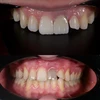

اعوجاج الأسنان

الأسنان المتفرقة